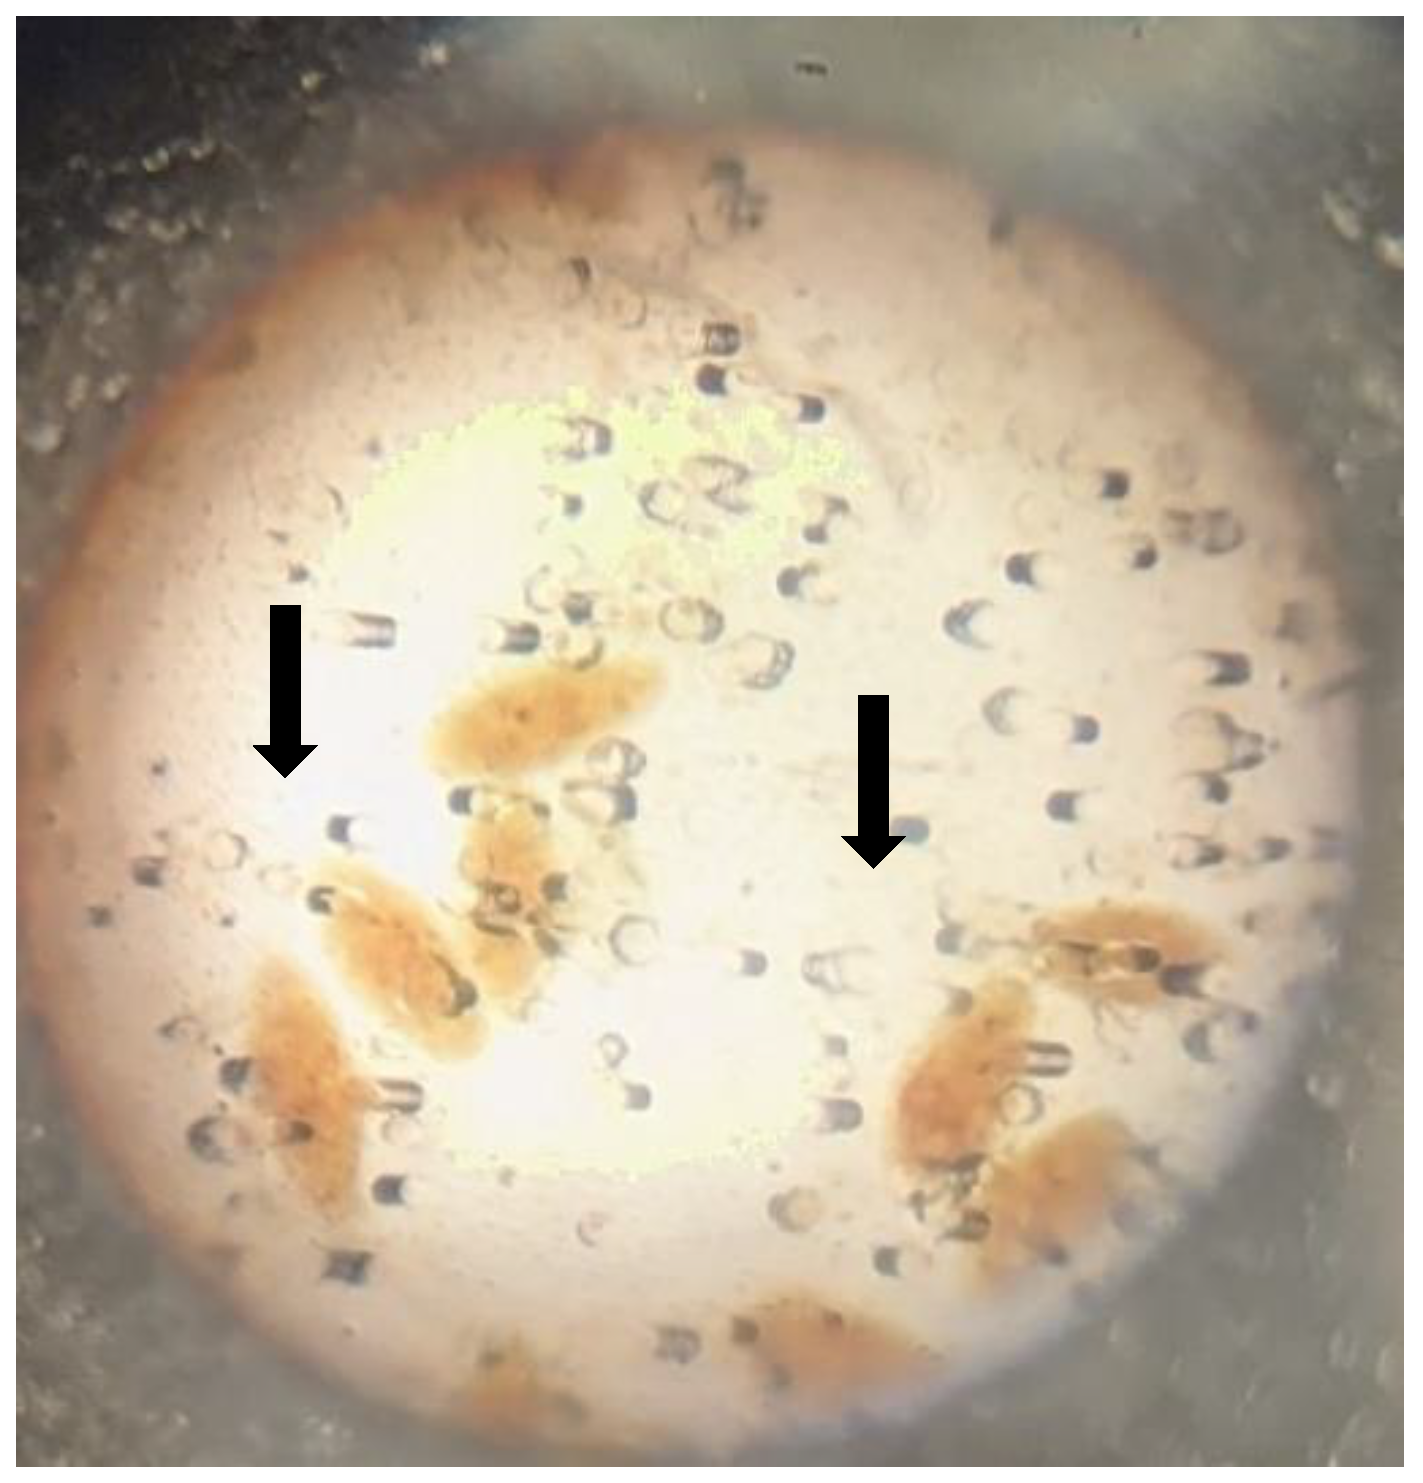

| Bulinus truncatus | Pulmonate | 2 | 2(100) | 0 | 0(0.0) | 0 | 0(0.0) | 0 | 0(0.0) | 2(0.49) |

4.7. Overall Snail Diversity and Abundance

3.6. Snail Survey

3.7. Examination of Snails for Patent Infection